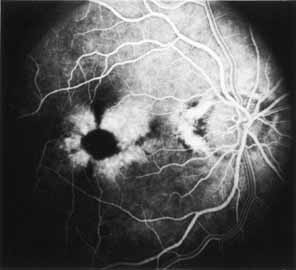

Although there is no reported genetic heterogeneity, there is wide phenotypic variation within the disorder. The major finding within the macula is a classic radial cystic maculopathy. Although retinal signs have been described in infants as young as 3 months, foveal schisis may be difficult to detect, leading to underdiagnosis. The diagnosis is usually not made until the affected male reaches school age (4 to 8 years of age) and encounters visual problems secondary to foveal involvement. Typical foveal schisis findings have been reported in 68% to 100% of eyes within various series.37,38 Foveal schisis is the only finding in about half the cases. It is characterized by the presence of radiate perifoveal microcysts located in the nerve fiber layer (Fig. 1) with radiate plications of the overlying internal limiting membrane that are seen especially well on monochromatic (red-free) photography (Fig. 2). The microcystoid change may slowly progress to form a macular cyst or hole. Foveal schisis has been reported in association with Goldmann-Favre vitreotapetoretinal dystrophy and rarely may be seen in rod-cone dystrophy or as an autosomal dominant or recessive condition.39–43